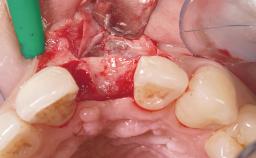

Immediate Flapless Placement of an Implant in a Maxillary Right Lateral Incisor Site

This 43-year-old male patient, a non-smoker, came to our practice because of a fracture of tooth 12 caused by a bicycle accident. Due to the combined para- and infrabony crown and root fracture, tooth extraction, and subsequent implant placement were suggested to the patient as the therapy of choice. The patient had high esthetic expectations with regard to the treatment outcome and asked for an immediate fixed provisional restoration. His individual esthetic risk profile summed up to a medium esthetic risk.

Placement Protocol Immediate implant placement

Socket Morphology Single-root socket

Socket Integrity Sufficient, with intact bone walls

Bone Volume Sufficient, with intact walls